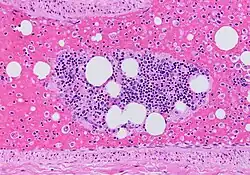

- On CT scan, pulmonary emboli can be classified according to the level along the arterial tree.

- Segmental and subsegmental pulmonary emboli on both sides

- CT pulmonary angiography showing a "saddle embolus" at the bifurcation of the main pulmonary artery and thrombus burden in the lobar arteries on both sides

- Pulmonary embolism (white arrow) that has been long-standing and has caused a lung infarction (black arrow) seen as a reverse halo sign